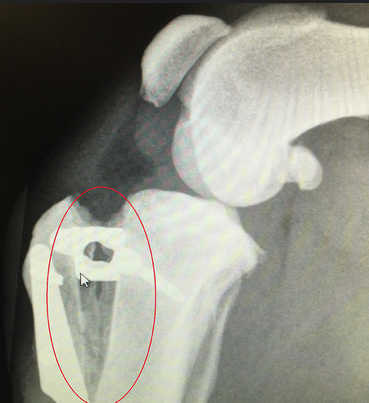

Tibial Plateau Levelling Osteotomy (TPLO)

Another option for CrCl disease treatment is TPLO. It is a more modern procedure, which involves more invasive surgery. A veterinary surgeon will make a circular cut in the tibia and realign the bone, to give a more stable base for the dog to walk on. This movement will be held in place by plates and screws. This method is sometimes preferred for larger, heavier dogs or for more active personalities.

Tibial Tuberosity Advancement (TTA)

Tibial Tuberosity Advancement (TTA) is similar in approach to TPLO. However, the bone is cut in a linear fashion, in order for the tibia to be moved to a different angle. Like TPLO it requires plates and screws to stay in place initially, and although they are not required after healing they are rarely removed. It also has a long period of recovery, where you will need to keep your dog on limited exercise to reduce the risk of re-fracturing the bone before it has healed.

The surgical procedures of both TTA and TPLO involve cutting the bone to change the angle of the tibial tuberosity in the stifle, using an implant to hold the bones in a different angle while they heal.

The Simitri Stable in Stride® implant is comprised of two, surgical grade stainless steel plates; the femoral (thigh bone) plate and the tibial plate. The femoral plate has a ball and stem that interconnects with the tibial plate via an 8 mm travel channel within the articulating insert.

The insert is composed of ultrahigh molecular weight polyethylene (UHMWPE), this is the same material used in human total hip and knee replacements. The plates are positioned on the inside of the affected leg and attached above and below the knee joint with six cortical locking screws. The entire implant remains outside the knee joint, but under the skin and muscle.